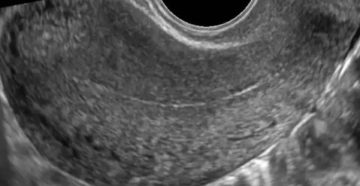

Расшифровка УЗИ малого таза у женщин Наверное, каждому посетителю кабинета УЗ-диагностики приходилось видеть на мониторе…